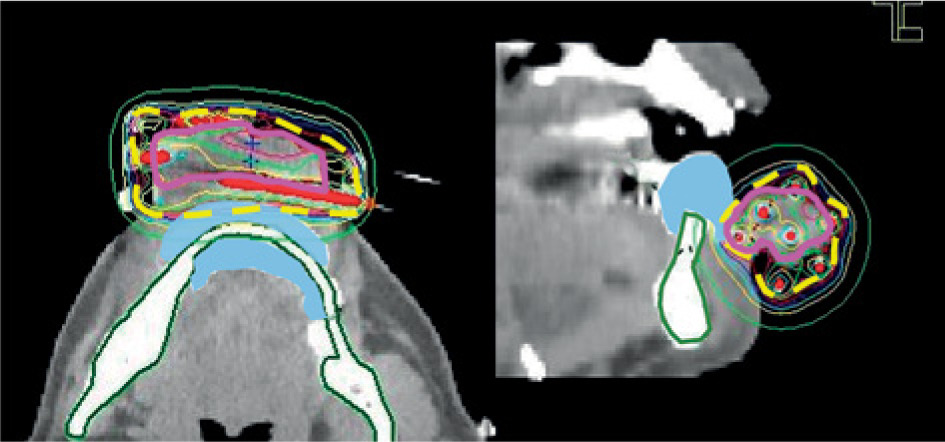

Fig. 3

Example of a dose distribution curve (case No. 1). The pink, yellow-dotted, and green lines represent the clinical target volume, 6 Gy isodose curve (as planning-aimed dose per fraction), and the mandible, respectively. The light blue area shows a silicone replica inserted instead of a lead shield to avoid metal artifacts for computed tomography